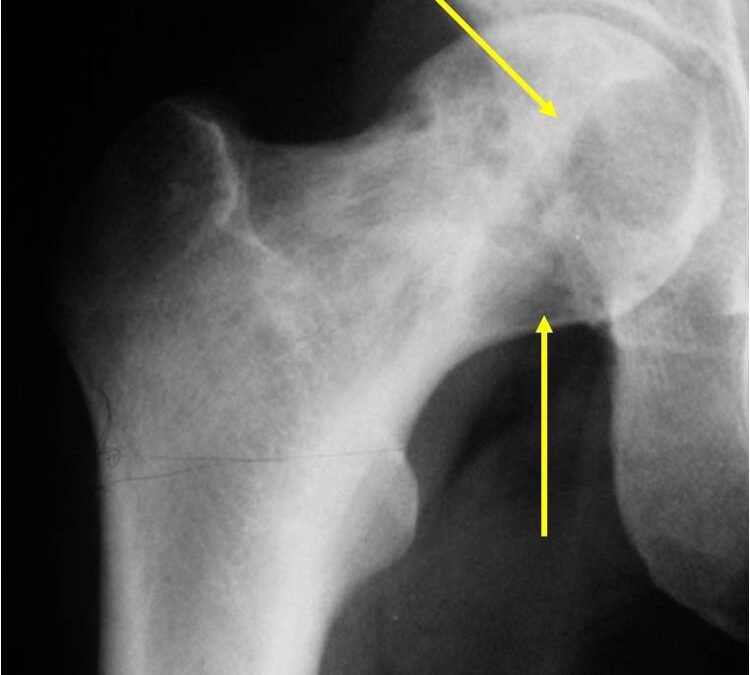

This is a malignant tumor or neoplasm composed of cartilage cells. It most commonly affects the ends of long bones such as the femur, humerus, and tibia.

A Conventional Chondrosarcoma is a cancerous bone tumor. It consists of cartilage located within the bone. It is a cancerous tumor, and can lead to bone destruction. It is a slow growing tumor that will not spread to other parts of the body in most cases.